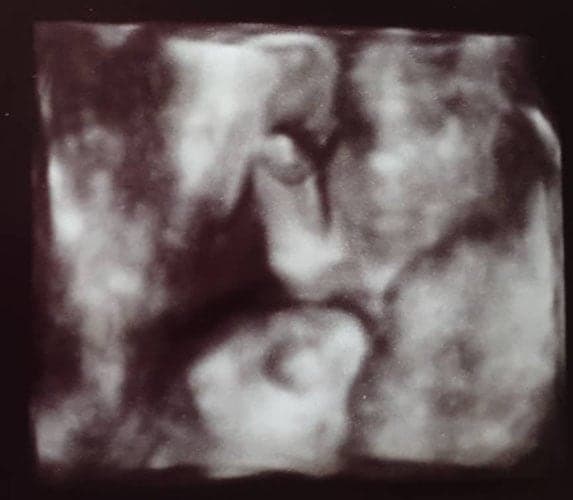

Ultraschallbilder aus dem 3. Trimester (29. bis 40. SSW)

Im dritten Trimester der Schwangerschaft ist das Baby so groß, dass es nicht mehr komplett auf ein Ultraschallbild passt. Nun kann man wunderbare 3D-Ultraschalle des Gesichts machen. In diesem Semester nehmen die Babys nochmal rasant zu und wer Glück hat, kann auf seinem Ultraschall schon erste Gesichtszüge erkennen.

Wer sich jedoch erhofft Gesichtszüge zu erkennen, der wird oft enttäuscht. Zwar kann man beim 3D-Ultraschall schon eine Menge sehen, aber das umgebende Fruchtwasser sorgt in den allermeisten Fällen für starke Störungen.